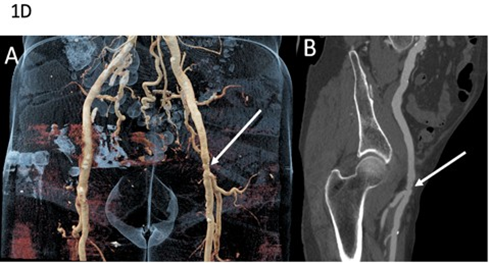

Fourth Case: A 60-year-old man was referred for suspected familial FMD. His medical history included arterial hypertension secondary to right renal artery dissection at the age of 36, initially diagnosed as FMD (Table 1). Seven years later, he experienced a right internal carotid artery dissection associated with a transient ischemic stroke. Subsequent CT imaging demonstrated additional arterial dissections involving the left renal artery, and the inferior mesenteric artery but ectasia and multiple irregularities and stenosis of the iliofemoral arteries were still suggestive of FMD (Figure 1D). Clinical examination revealed venous insufficiency, spontaneous bruising, thin translucent skin, keloid scarring, and facial features suggestive of vEDS. Molecular testing identified a pathogenic splice-site COL3A1 variant, which was subsequently detected in his daughter, who also exhibited minor signs of vEDS, as well as in several relatives previously diagnosed with FMD (Figure 2D).

Figure 1D: Arterial imaging of patient 4 on computed tomography angiography (CTA). CTA in a 79-year-old man showing vascular abnormalities. Coronal volume-rendered image (A) depicts ectasia and multiple stenoses of the left external iliac artery (arrow). Curved planar reformation (B) shows alternating areas of relative stenosis and small aneurysms of the left external iliac artery (arrow). Molecular diagnosis of vascular Ehlers-Danlos syndrome was established after imaging.